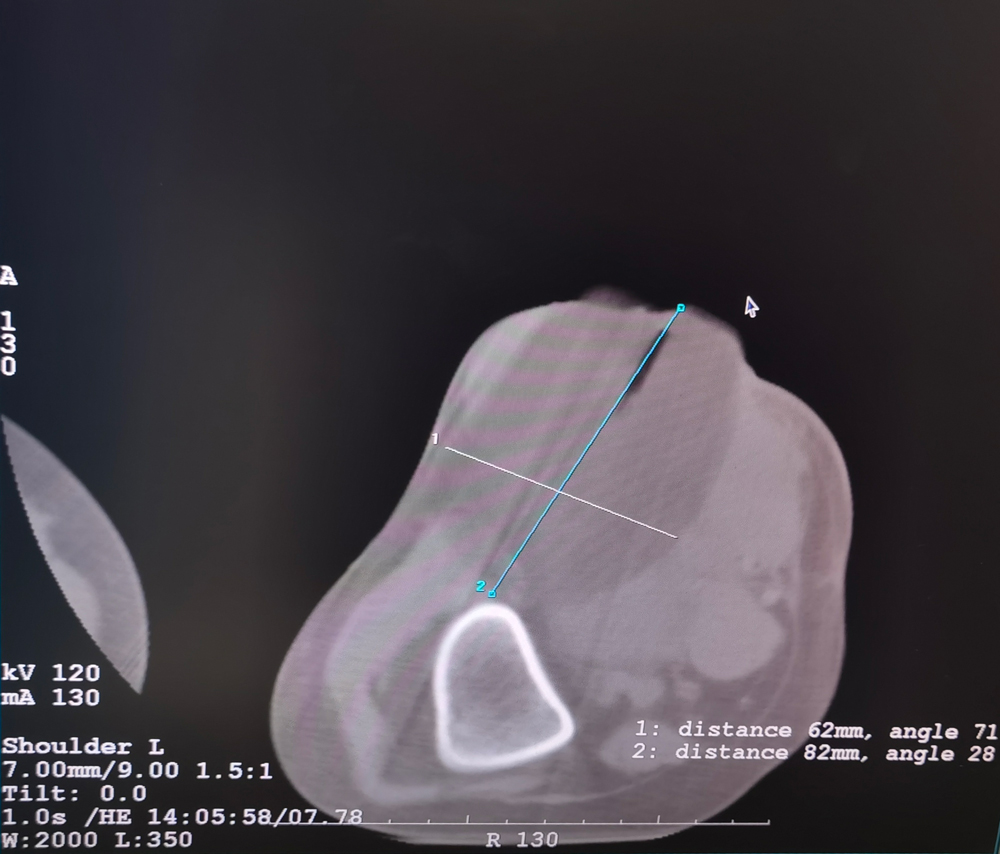

當地時間3月8日,土耳其知名專家Yilmaz教授在Varisson Interventional Radiology Clinics,成功為兩名腫瘤患者完成復合式冷凍消融術,患者術后狀況良好。Yilmaz教授對康博刀給予了高度評價,清晰的治療邊界、極致溫差、單針最大治療區域等技術優勢有效保障了治療安全及患者獲益。本次手術是海杰亞醫療康博刀的首次海外臨床應用,是腫瘤微創介入治療領域的國產原創高端醫療技術,成功實現了反向輸出海外醫療的標志性事件。